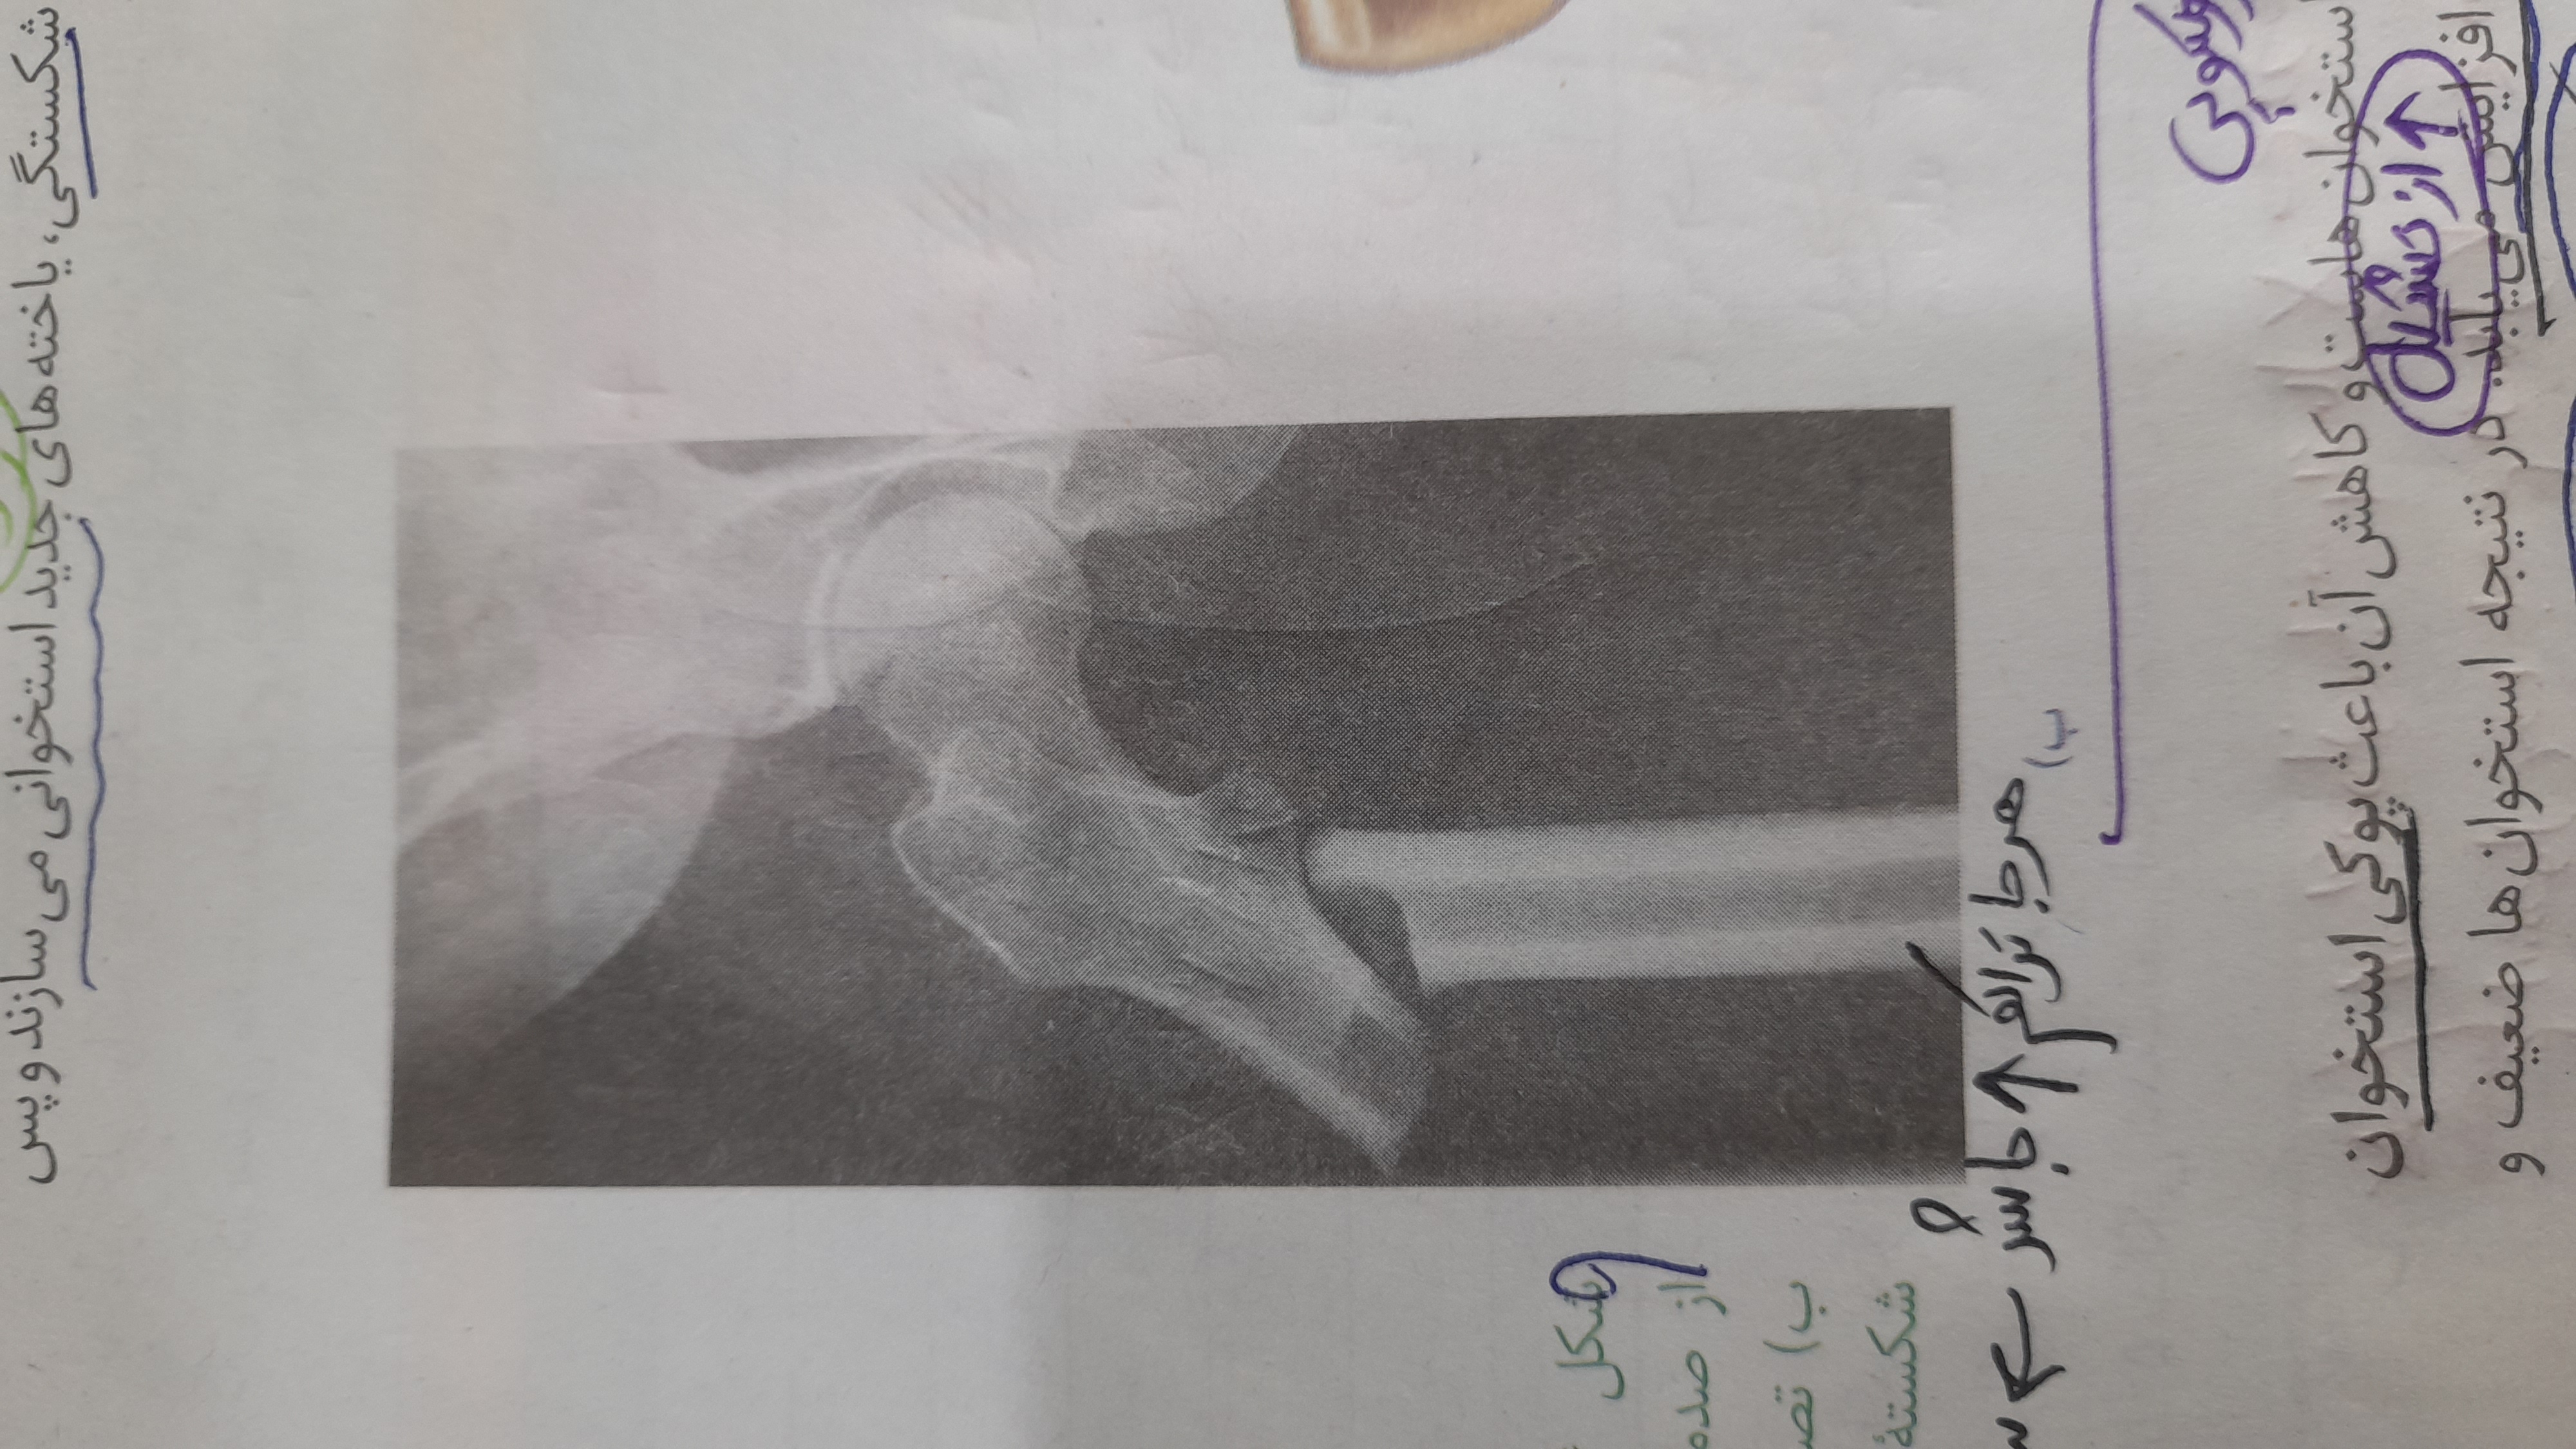

این نکته کتاب فقط در صورتی درست هست که شکستگی از نوع ترک باشه و جابه جایی استخوان نداشته باشیم. درست متوجه شدم؟؟ خط اول که استاد نوشتن میتوز رو میگم.

(1)

ببین در واقع در هر دو حالت، یاخته های استخوانی این تقسیمات میتوزی رو برای ترمیم انجام میدن چه شکستگی میکروسکوپی و چه شکستگی در مقیاس بزرگتر(که در این حالت،اون ناحیه رو مثلا گچ میگیرن که لبه های استخوان به هم بچسبه و پس از مدتی جوش بخوره )🌷🌷

@سید محمد متین رشادی بله اما من منظورم این بود گه مثلا مثل تصویر کتاب که کلا استخوان در رفته و سر جاش قرار نگرفته خب الان هم با وجود اینکه فقط عمل جراحی باید انجام بشه باز هم یاخته های استخوانی در محل شکستگی یاخته استخوانی جدید می سازن؟؟ اگر این کار رو بکنن که فایده نداره و با ماده زمینه بیشتر قطعا این استخوان خوب نمیشه! امیدوارم منظورم رو متوجه شده باشید